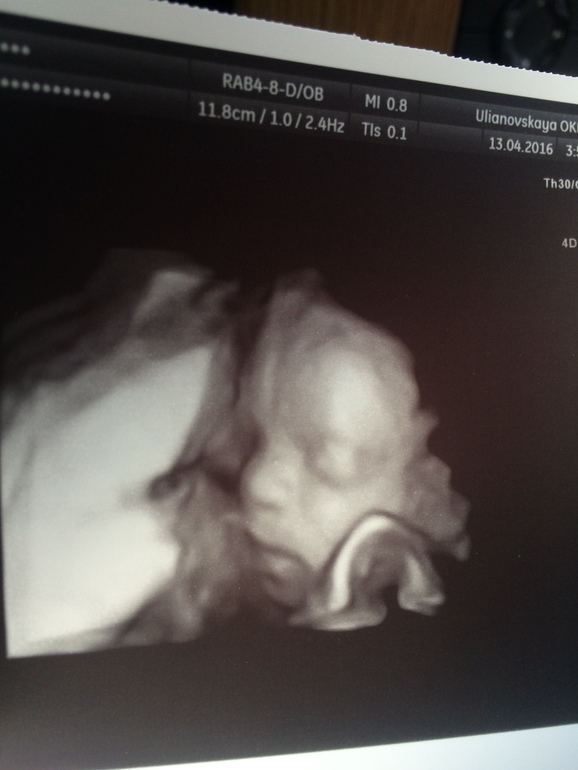

УЗИ, КТГ, доплерОт УЗИ, а конкретнее от узистки я не в восторге.. Есть хорошие новости и не очень.. Под кат Малыш соответствует 23 неделям.. Развиваемся хорошо☺️ Весим 492 грамма..😍😍😍 носик 6,2мм, ЧСС 156..)) БПР 56мм, ЛЗР 73 мм, ОГ 204мм, ОЖ 173мм..)) количество вод нормальное..)) все тьфу тьфу..)) ☺️малыш махал кулочками, шлепал губами, потом нахмурился, вытянул губы в трубочку и отвернулся)))🙄пришлось погулять, погладить, чтобы он повернулся обратно..))) Наконец то поднялась плацента!😊 В принципе все отлично, за исключением ШЕЙКИ! 25мм, закрыта на всём протяжении... У меня паника.. Завтра записываюсь к своему платному врачу..что то надо делать..очень страшно.. Ну и фото моего котёнка❤️❤️❤️

Настюш, ну как ты? К врачу ходила? Шейка конечно расстраивает, что-то она рано укоротилась... Но это не безвыходная ситуация, можно поставить писсарий и спокойно доходить до полного срока. Это как-то связано с твоим тонусом? Зато какой малышонок хорошенький 😍😍😍 просто как с картинки! Часто на 3Д детки получаются не самыми симпатичными, а у тебя прям как с картинки 👶🏼👍🏼💁🏼 такой лапочка!!! 😘

Спасибо, Маш..))) да тут непонятно ещё.. Мне кажется на папу..)) губы уже полные как у папы.. А носик вроде на мой больше похож, но острый как у папы..)))) на всех похож)))

Да я хотела в 20 нед 3Д сделать, мне сказали давай лучше 23-24 придешь, малыш уже поприкольнее, потолще, заодно и эхо-кг сделаем..)) я согласилась..))